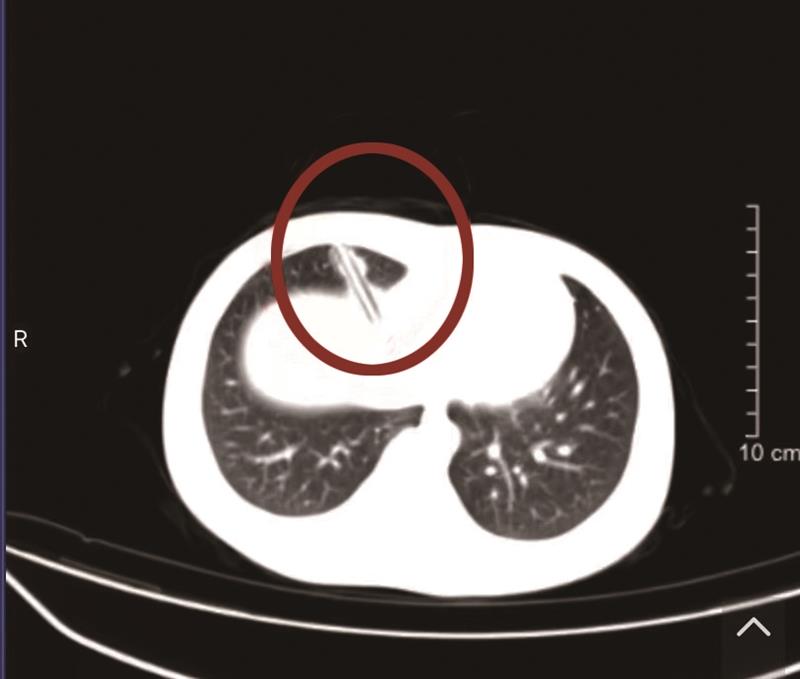

该院心胸外科副主任医师吴国伟接到电话后,随即赶到急诊科查看伤者影像检查报告,发现铅笔插在胸腔和腹腔的连接处,穿透了膈肌,紧贴着心脏、肝脏以及肺部(见左图)。

该院心胸外科连夜给小倩做手术。术中医生发现,留在体内的铅笔长7厘米,穿透了胸壁,把膈肌也捅破一个窟窿,而且穿过心脏心包前方的脂肪,离心脏不到0.5厘米,铅笔随着心跳和呼吸在摆动,笔尖下方就是肝脏和大血管,万幸的是心脏肺和肝脏都没有伤及。一个小时后,医生小心地拔出了扎在小孩胸腔的铅笔,修补了破损的膈肌,给予充分的消毒清创后缝合了伤口。